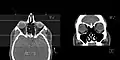

CT scan of the paranasal sinuses with coronal reconstruction (right) and axial planning data (left).